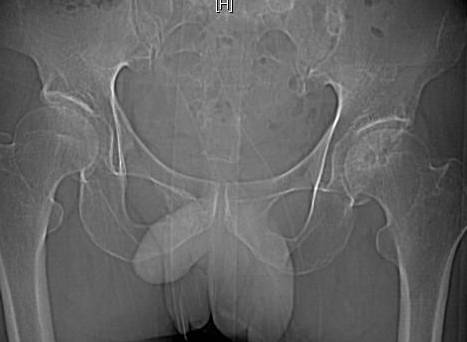

髋关节平扫

对髋关节脱位进行准确分型并可判断脱位的距离及程度;合并髋臼骨折时对骨折片的数目、大小及来源可作出准确判断;对关节腔内游离骨折片的检出明显优于X线平片;能清楚显示关节囊及盆腔损伤情况。